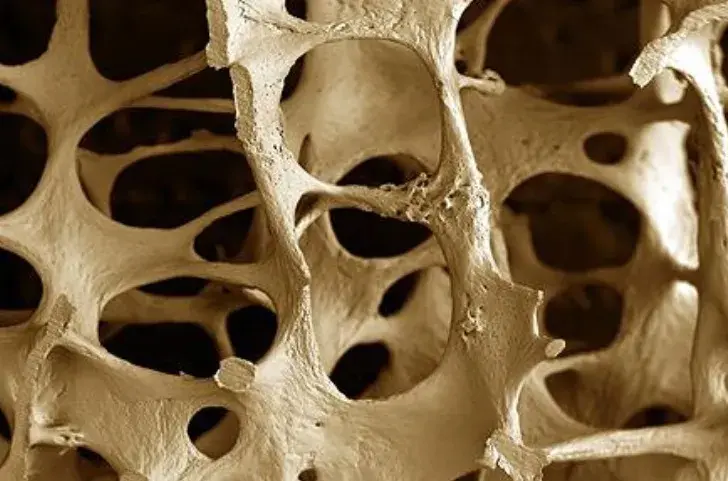

Injúria Renal Aguda (revisão Lancet 2025)